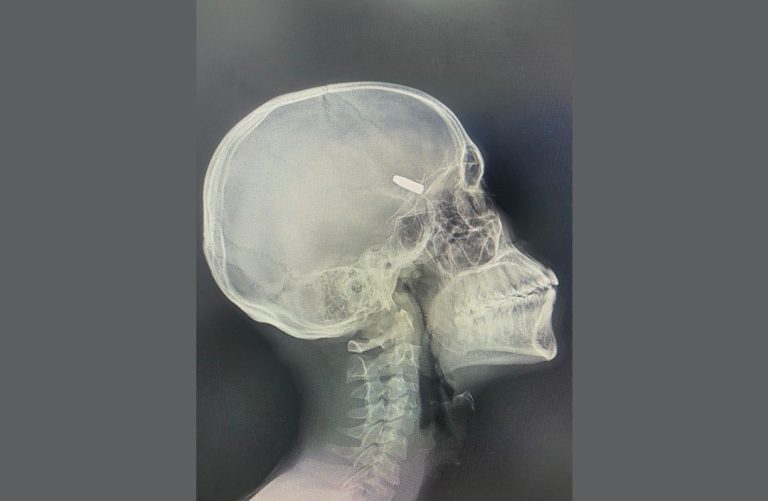

Une technologie exclusive en Afrique centrale

Le Congrès marque également l’introduction de la neuronavigation, une technologie chirurgicale de pointe encore inédite en Afrique centrale. Elle permettra d’effectuer des interventions d’une précision exceptionnelle, ouvrant de nouvelles perspectives à la neurochirurgie congolaise.